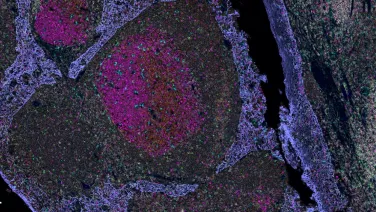

CHASM Histology

Immunohistochemistry - single and multiplex fluorescence and chromogenic staining